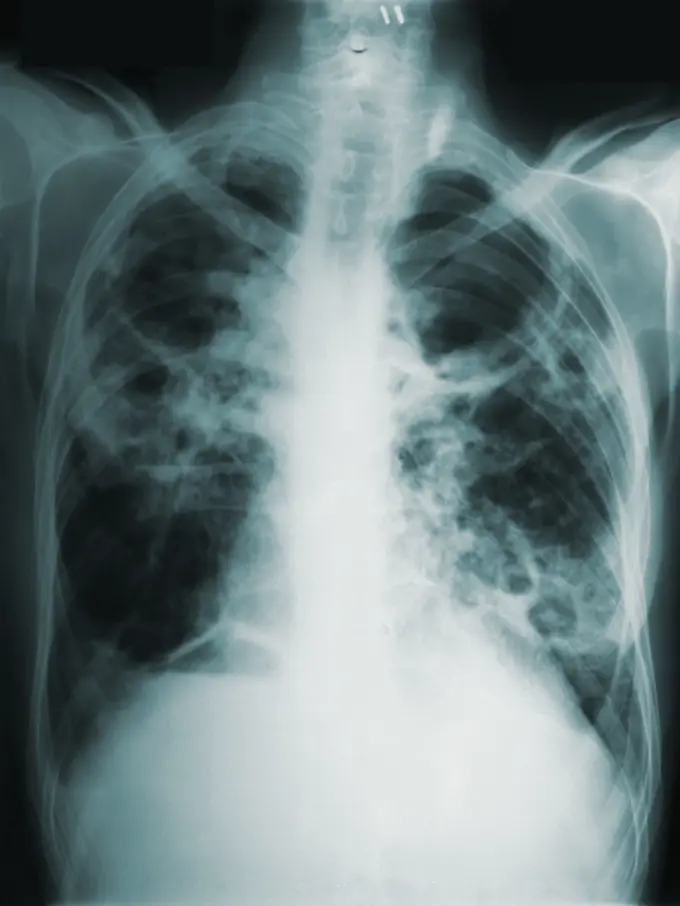

Fimela.com, Jakarta Sahabat Fimela, tahukah Anda bahwa Tuberkulosis (TB) masih menjadi ancaman serius di Indonesia? Negara kita menduduki peringkat kedua secara global untuk beban kasus TB tertinggi, dengan estimasi jutaan kasus baru setiap tahunnya.

Angka kematian akibat TB juga memprihatinkan, mencapai sekitar 14 kematian setiap jam pada tahun 2024. Kondisi ini menuntut inovasi dan solusi cepat untuk mempercepat penanganan penyakit menular ini di seluruh pelosok negeri.

Penanganan TB di Indonesia menghadapi berbagai kendala kompleks yang menghambat upaya eliminasi pada tahun 2030. Salah satu masalah utama adalah deteksi dini yang rendah dan kesenjangan penemuan kasus, di mana banyak kasus TB belum terdiagnosis karena keterbatasan akses layanan kesehatan.

Selain itu, ketidakpatuhan pasien dalam menyelesaikan pengobatan menjadi isu krusial. Durasi pengobatan TB yang panjang, terutama untuk TB resisten obat (TB RO), seringkali membuat pasien putus berobat, meningkatkan risiko resistensi obat yang lebih sulit ditangani.

Indonesia juga dihadapkan pada tantangan besar dalam penanggulangan TB Resisten Obat (TB RO). Keterbatasan sumber daya, infrastruktur, dan kesenjangan pelatihan tenaga kesehatan dalam menerapkan paduan pengobatan baru menjadi penghalang signifikan. Stigma sosial dan beban ekonomi juga memperburuk kondisi pasien.